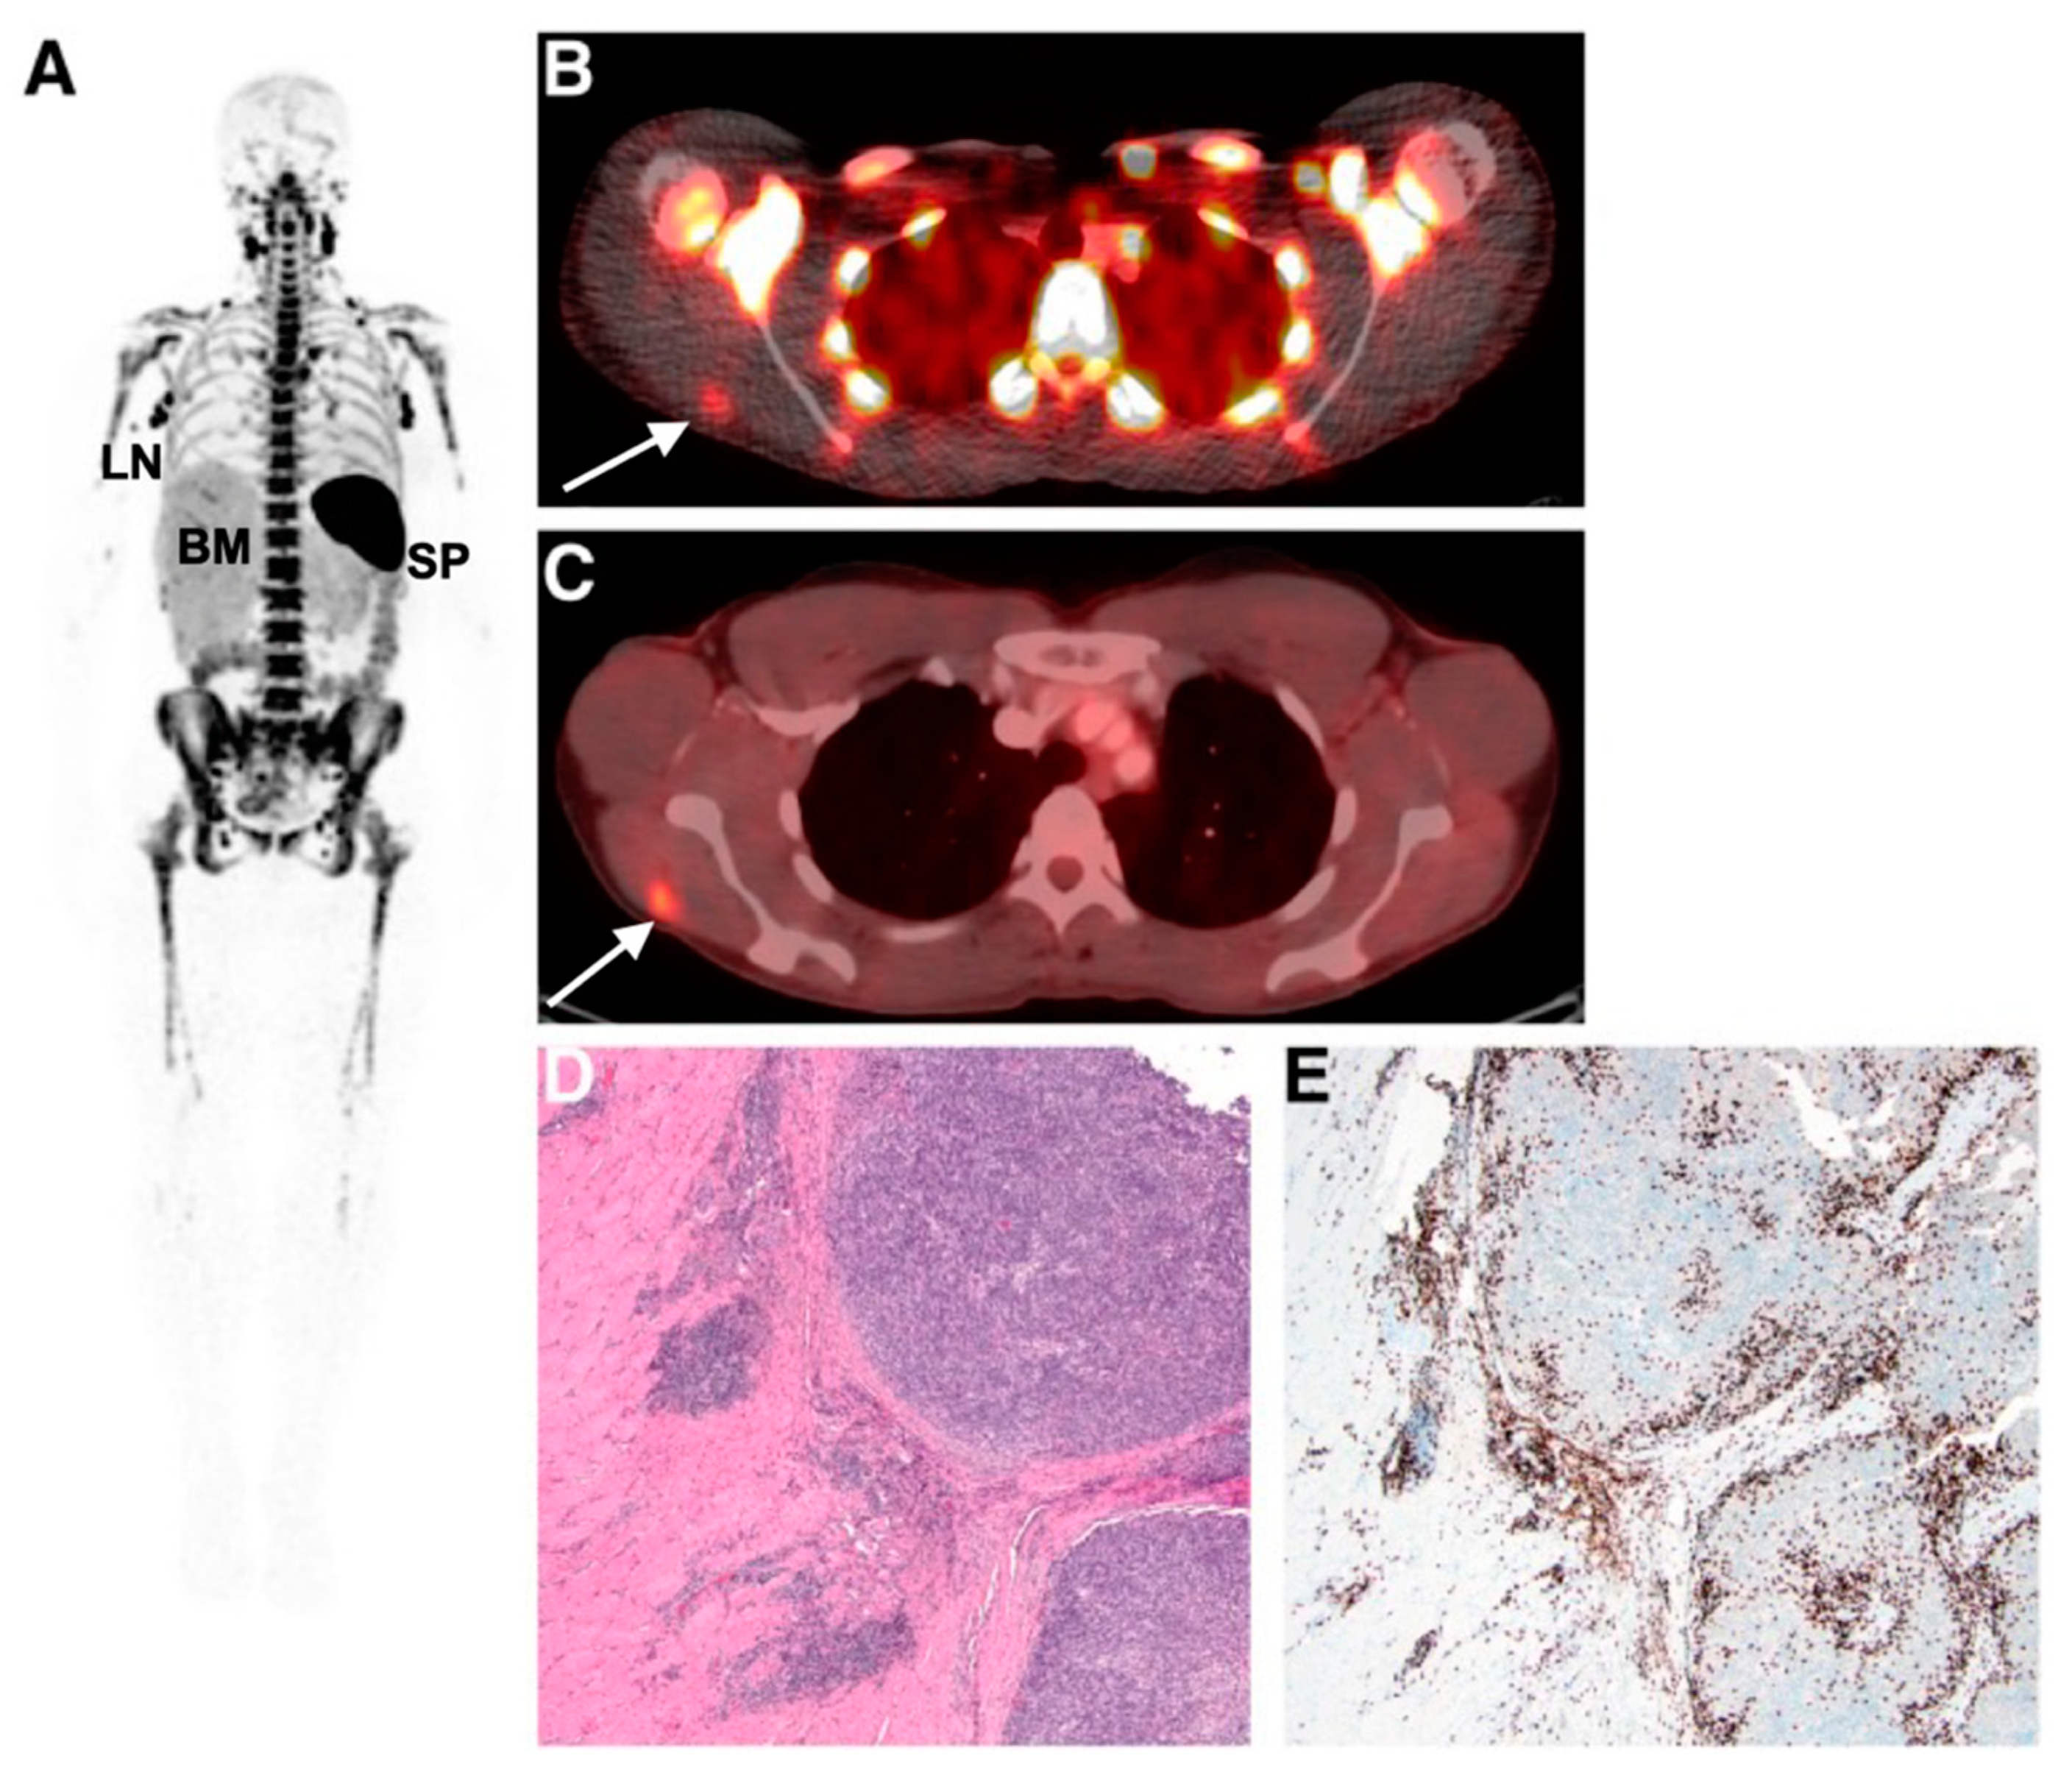

Imaging and detecting the presence of therapeutic T-cells in tumours has been demonstrated using CD8 antibody fragments (Figure 4) [86,87,88]. For example, CD8 cys-diabodies ([89Zr]Zr-malDFO-169 cDb) engineered from rat hybridoma cell lines have been used for the non-invasive tracking of cytotoxic T-cells in murine models of cancer immunotherapy [86]. A higher uptake of the tracer was detected in ovalbumin-expressing tumours following adoptive transfer of CD8+ T-cells expressing the MHC Class I-restricted TCR specific for ovalbumin (Ova) [86]. Preliminary data from a first-in-human study on six patients using [89Zr]Zr-IAB22M2C, a radiolabelled minibody targeting CD8, demonstrated favourable pharmacokinetics and a good safety profile [87]. Tracer uptake in CD8+ T-cell-rich tissues such as the lymph nodes was seen as early as 2 h post-injection. Tumour uptake was noted in two patients receiving immunotherapy (metastatic melanoma and hepatocellular carcinoma), but not in the remaining four patients with lung metastases. The tumour uptake of [89Zr]Zr-IAB22M2C was also histologically confirmed as CD8+ T-cell infiltration at the periphery of a metastatic lesion in the deltoid muscle of a patient with melanoma. The uptake of [89Zr]Zr-IAB22M2C in tumours showed areas of both concordance and discordance with [18F]FDG-PET uptake, in addition to non-specific uptake in bone marrow and lymph nodes. Therefore, [89Zr]Zr-IAB22M2C can be used as a complementary tracer to [18F]FDG for the direct imaging of CD8+ T-cells.

Figure 4.

Imaging human T-cell tumour infiltration using [89Zr]Zr-IAB22M2C, a radiolabelled minibody targeting CD8. (A) Normal splenic, bone marrow, and lymph node uptake of the tracer were observed. Uptake of (B) [89Zr]Zr-IAB22M2C and (C) [18F]FDG in a melanoma metastasis in the deltoid muscle of a patient was histologically confirmed as high CD8+ T-cell infiltration (D,E). Figure reproduced from [87].